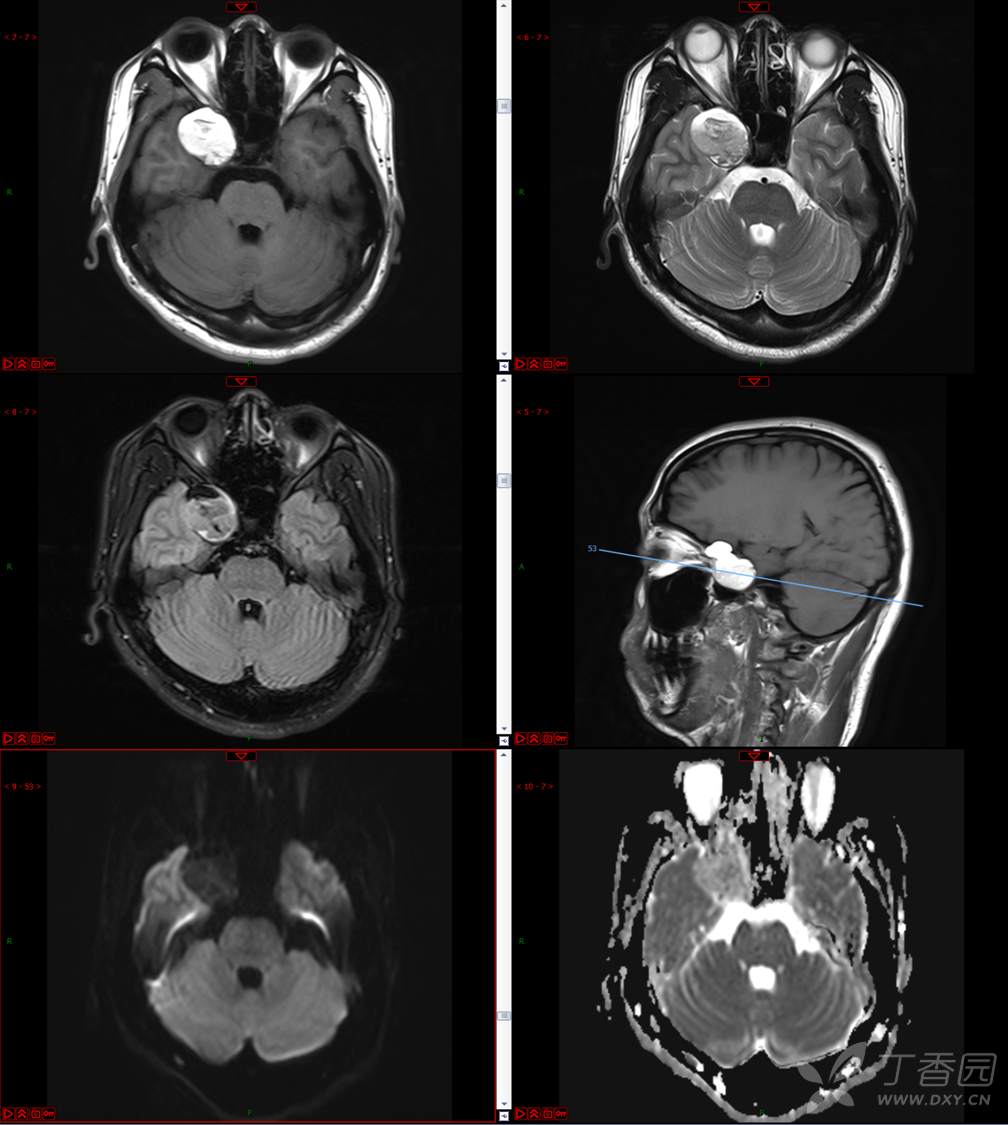

【影诊笔记534】青年男性,视物模糊就诊,CT、MRI、MRS齐全,请分析~~~

主 诉:视物重影5天。

现病史:患者5天前无明显诱因出现视物重影,表现为右视时视物成双,无头痛、头晕,无恶心、呕吐,无面部麻木、饮水呛咳等,于当地医院就诊,行颅脑MR示“颅内占位性病变”,现为求进一步治疗来诊。患者病来精神可,饮食、睡眠正常,体重无明显变化。